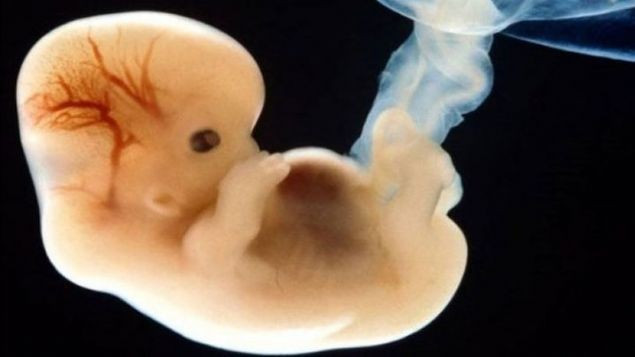

Tarihte ilk kez insan genleri bu araştırmada başarıyla değiştirildi.